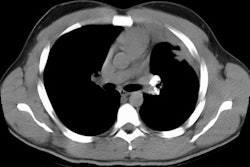

Thesaurosis:

Clinical:

Thesaurosis is associated with the inhalation of hair spray and it is especially common in beauticians. The radiologic features are indistinguishable from sarcoid and some pathologists believe thesaurosis is not an independent entity, but merely sarcoid.